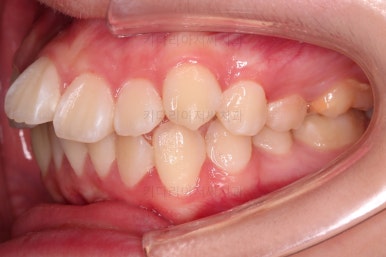

부산덧니교정 마무리를 한 모습인데요.

가지런한 모습 좋고, 교합이나 중앙선 등 매우 잘 맞네요.

전후를 비교해 볼게요.

치열, 교합, 악궁의 형태 매우 좋아졌어요.

입이 매우 나와있을 때 턱끝에 힘이 들어가는 습관이 아직 개선되지 못했는데 힘 빼고 다무는 연습을 좀만 더 해준다면 옆라인도 훨씬 좋아질 것 같았어요.

전반적으로 만족스러운 치료였습니다.